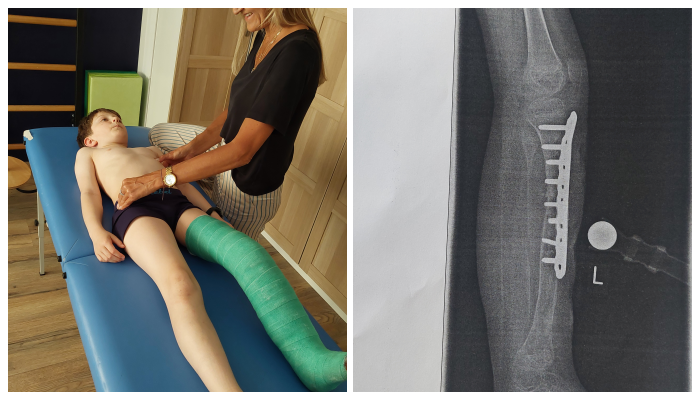

Aby tak się stało, musimy zgromadzić środki potrzebne do ich opłacenia.Bruno cały czas dzielnie pracuje pod okiem najlepszej fizjoterapeutki – Pani Izy, z którą znają się od urodzenia, aby minimalizować problemy związane z długotrwałym noszeniem aparatu Ilizarowa, a teraz gipsu. Chce być w jak najlepszej kondycji i wreszcie wrócić do zabawy z kolegami.

Prosimy, pomóżcie Brunowi w jego walce o zwyczajne dzieciństwo. Bruno marzy, żeby od września móc wreszcie wracać samodzielnie ze szkoły z kolegami tramwajem...

W jego przypadku biletem na tramwaj są.... ortezy warte 23000 euroPILNA aktualizacja 📣